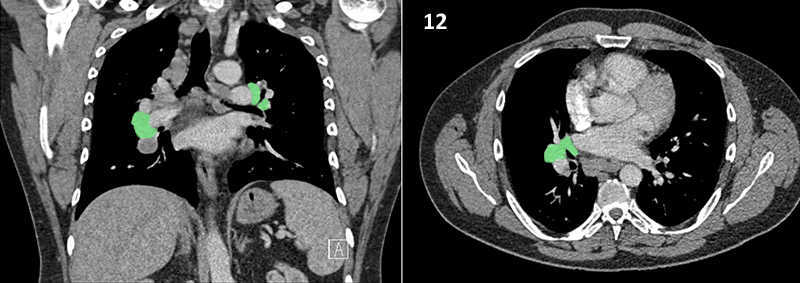

Nodal zones and stations according to the International Association for the Study of Lung Cancer (IASLC) node map.

Table (above): Nodal zones and stations according to the International Association for the Study of Lung Cancer (IASLC) node map. (Source: 1,2) *Depends on the side of the tumour.